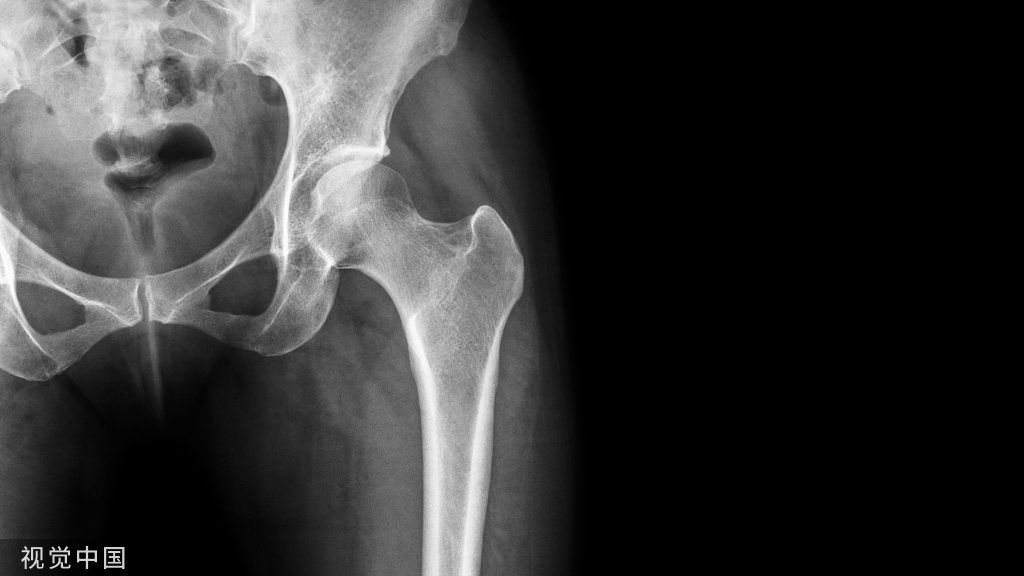

01髋臼骨折

髋臼骨折最常见的类型是髋臼后壁骨折,几乎占髋关节骨折的 1/4,且常常合并髋关节后脱位。由于骨性结构重叠,可能肉眼看上去觉得非常轻微的骨折,事实却并非如此。髋臼后缘中断常常是髋臼后壁骨折的一个特征(图 2)。